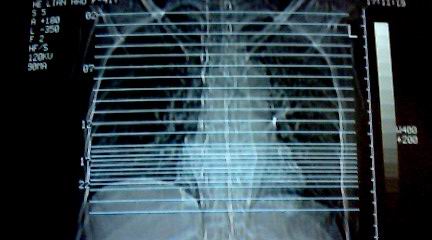

标题: CT25218:请教!胸部CT,胸8椎体骨质破坏,伴周围软组织肿。 [打印本页]

标题: CT25218:请教!胸部CT,胸8椎体骨质破坏,伴周围软组织肿。

两肺上叶继发性肺结核;胸椎结核并椎旁寒性脓肿形成。

两肺上叶继发性肺结核;胸椎结核并椎旁寒性脓肿形成

恶性,椎体淋巴瘤或pnet并肺内转移。